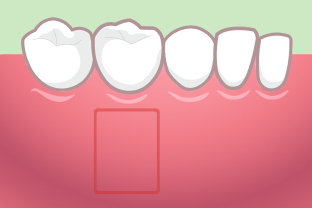

歯肉移植による長期的な治療効果の解説図

歯肉退縮が起きると、進行を止めることはできても、自然に回復することはありません。そこで、治療法として用いられるのは、「歯肉移植」によって、上あごなどの他の部分から歯肉を移植する方法です。

歯肉退縮治療をおこなった後に、時間が立つともとに戻ってしまうことを心配される方もいらっしゃるかと思います。

そのお答えとして臨床研究では、歯肉移植を行い歯肉退縮を回復させて10年〜35年たった後、もとに戻るどころか、さらに歯肉が増える(83%の症例)との報告があります。(e.g. Agudio G, J Periodontol. 2016 Dec;87(12):1371-1378.)

図は、左側で歯肉移植をした場合、歯肉が回復してく様子を、右側では、歯肉移植をおこわなかった場合、除々に歯肉退縮がひどくなっていることを示しています。